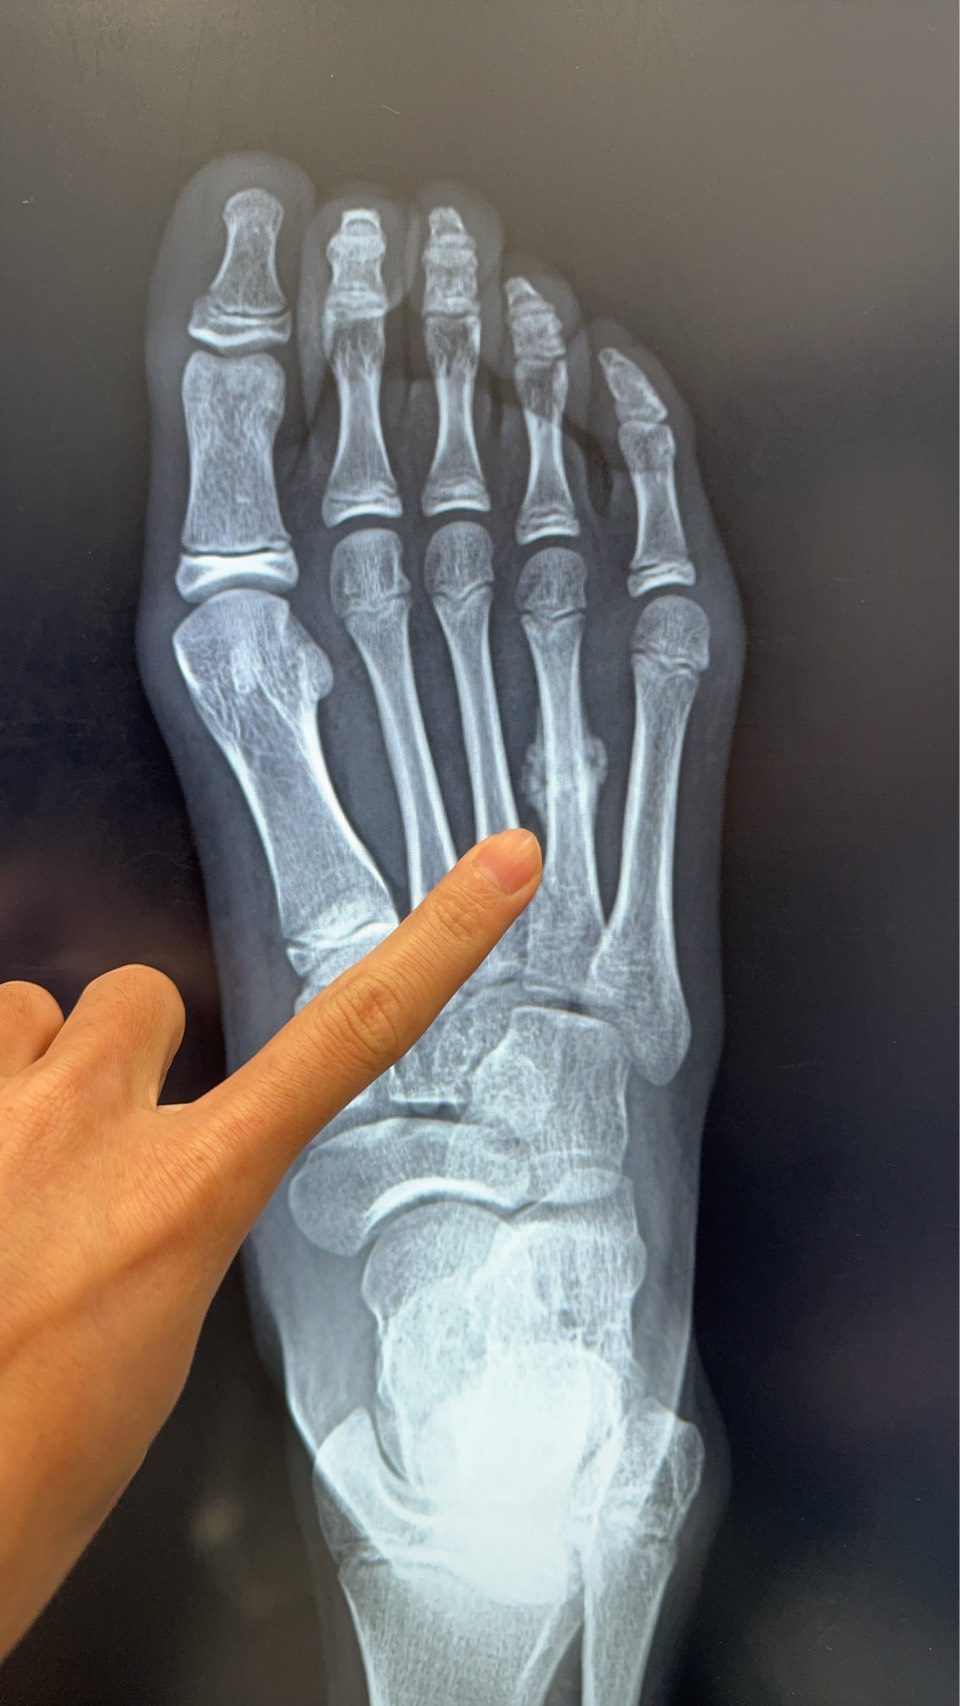

近日,陳建宏骨科診所接獲一名11歲女學童就醫個案,該學童因暑期密集參加田徑與球類訓練,右側腳掌疼痛兩周未緩,檢查後確診為「蹠骨應力性骨折」,且已出現癒合跡象。

▲11歲女學童右側腳掌「蹠骨應力性骨折」,且已出現癒合跡象。

與一般一次性外力造成的骨折不同,「應力性骨折」大都是長時間累積而成,初期症狀並不明顯,容易被誤為只是一般的拉傷或扭傷。就像此位11歲的小妹妹,問診詢時已經不舒服兩周,當初本以為只是單純扭到,沒想到卻已經骨折了。